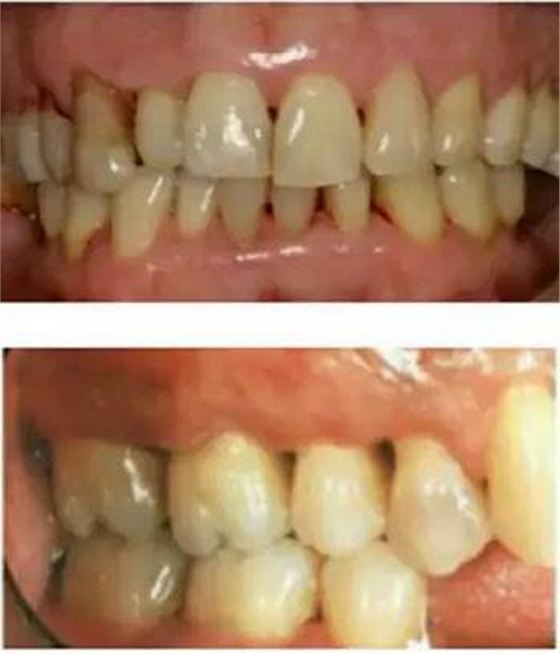

在猶疑之中,在未作任何牙周治療的情況下,牙齦出血可能突然減少或停止,很多患者慶幸自己的牙齦出血好了,其實是牙周病更加加重了,因為牙齦過度腫脹后,營養(yǎng)終于跟不上,導(dǎo)致了毛細血管的萎縮,因此會出現(xiàn)牙齦出血減少或停止的現(xiàn)象。但是同時牙槽骨也在喪失,于是,牙縫變稀變大(如上圖所示),更易殘留食物,口臭加重,牙根部分暴露,可能有冷熱刺激敏感。

1.牙周病矯正: 牙周病人前牙唇傾,間隙變大,可戴矯正器關(guān)閉間隙。